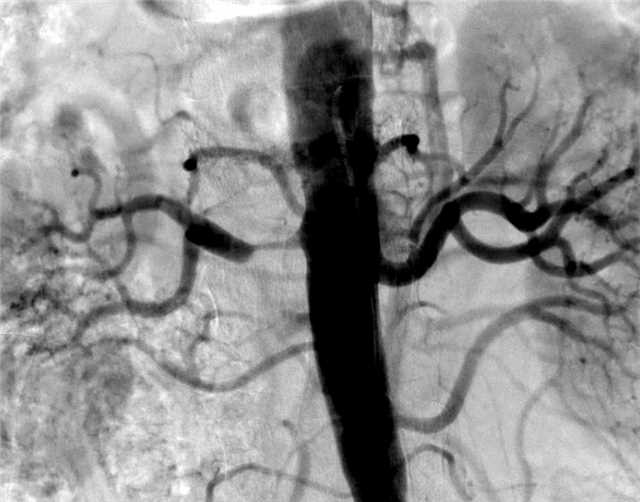

腎動脈狹窄最常見的原因是動脈硬化,主要見于老年病人,約占腎動脈狹窄患者的80%,另外20%腎動脈狹窄的病因常見于大動脈炎及腎動脈纖維肌發(fā)育不良,主要是年輕女性病人居多。腎動脈狹窄會引起的難以控制高血壓,其病人特點是發(fā)病年齡偏輕,40歲以下,病情發(fā)展較快,55歲以上者原有長期的高血壓突然加重,原有的降壓藥物難以控制血壓,需要增加降壓藥物的劑量及種類。這種腎動脈狹窄引起的高血壓早期表現(xiàn)就是高血壓難以控制,由于腎臟對缺血敏感,所以很快就表現(xiàn)為腎功能減退,出現(xiàn)夜尿多,尿比重及滲透壓減低,進一步腎小球功能受損硬化萎縮,表現(xiàn)為血肌酐增高,腎臟萎縮。隨著時間的推移還會引起頸動脈、腦動脈、心臟冠狀動脈以及下肢動脈硬化閉塞,只有盡早解除腎動脈狹窄或阻塞,病變血管重新通暢后,高血壓才可被控制,腎功能減退才可以好轉(zhuǎn)。腎動脈狹窄性高血壓需要做哪些檢查來診斷病情?首先需要完善彩色多普勒超聲,可以早期發(fā)現(xiàn)腎動脈狹窄并測定腎臟血流速度,簡單易行又無創(chuàng),同時還能觀察到腎臟有無萎縮。其次,如果彩超發(fā)現(xiàn)腎動脈狹窄或腎臟萎縮了,可以繼續(xù)完善腎動脈CTA或MRA檢查,也就是增強CT或MRI。增強CT掃描比核磁共振快速,其敏感性和特異性分別可達98%和94%,在門診即可完成然后,需要做核素腎血流圖檢查,用于檢測腎臟分腎功能,評估腎功能受損情況,為治療腎動脈狹窄提供依據(jù)。最后,入院進一步做腎動脈造影術(shù)。腎動脈造影是診斷腎動脈狹窄的“金標準”,可反映腎動脈狹窄的部位、范圍、程度、病變性質(zhì)、遠端分支及側(cè)支循環(huán)情況,并可以通過測壓導(dǎo)絲測量狹窄近端及遠端動脈壓力變化,可觀查腎臟形態(tài)和功能改變,可以決定是否需要做腎動脈成形術(shù)(球囊擴張或者支架)。腎動脈狹窄引起的難以控制高血壓需要介入支架治療,內(nèi)科藥物治療能幫助控制高血壓,改善癥狀,同時也是維護支架后長期通暢率必要保障。腸溶阿司匹林、氯吡格雷、他汀類降脂藥物都是延緩全身動脈硬化進展的常用藥物,降壓藥物種類很多,單側(cè)腎動脈狹窄呈高腎素者,現(xiàn)常首選ACEI或ARB類降壓藥物,但是必須從小量開始,逐漸加量,以免血壓下降過快過低。雙側(cè)腎動脈狹窄者腎功能不全者應(yīng)禁服上述藥物。為有效控制血壓,常需內(nèi)科多種降壓藥物配伍應(yīng)用。持續(xù)高壓吃藥后降不下來?不妨聽聽兩位教授在養(yǎng)生堂節(jié)目中是怎么說,什么樣的高血壓跟腎動脈狹窄有關(guān)?